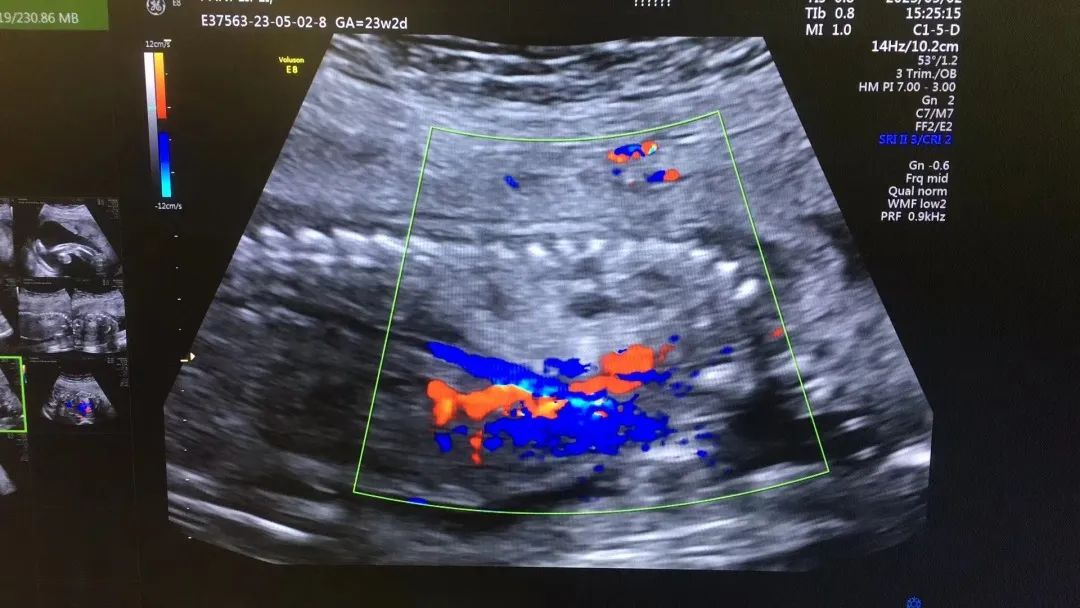

近日,我院超聲科醫(yī)生在給孕中期孕媽做四維彩超檢查時(shí),發(fā)現(xiàn)胎兒查出異常,孕媽想留下這個(gè)寶寶,陷入了兩難。

武漢的劉女士(化名),前幾個(gè)月剛懷上寶寶,全家都特別高興。懷孕23周+時(shí),劉女士在家人的陪伴下來到武漢仁愛醫(yī)院超聲科做了四維彩超檢查,當(dāng)醫(yī)生拿出檢查報(bào)告的時(shí)候,劉女士卻當(dāng)場(chǎng)傻眼了,原來,在四維彩超的報(bào)告里,診斷出了胎兒右肺囊性腺瘤樣病變,她的心頓時(shí)揪了起來!

劉女士看到檢查結(jié)果后,擔(dān)心該病變會(huì)影響腹中寶寶的健康,考慮是否應(yīng)該終止妊娠。隨即,武漢仁愛醫(yī)院超聲科王娟主任為劉女士耐心地解釋:“先天性肺囊腺瘤是一種肺組織錯(cuò)構(gòu)畸形,先天性肺囊腺瘤畸形病例約70%的腫塊大小較穩(wěn)定;約20%腫塊產(chǎn)前明顯縮小或消失;僅10%腫塊是進(jìn)行性增大。單純的先天性肺囊腺瘤(CCAM)無水腫的胎兒可以密切隨訪,在28周前接受連續(xù)超聲復(fù)查,CVR<1.6,一般超聲動(dòng)態(tài)監(jiān)測(cè)2~4周監(jiān)測(cè)一次,而對(duì)于CVR≥1.6的需要在28周前每周1-2次的超聲監(jiān)測(cè),防止出現(xiàn)胎兒水腫,直到分娩。”